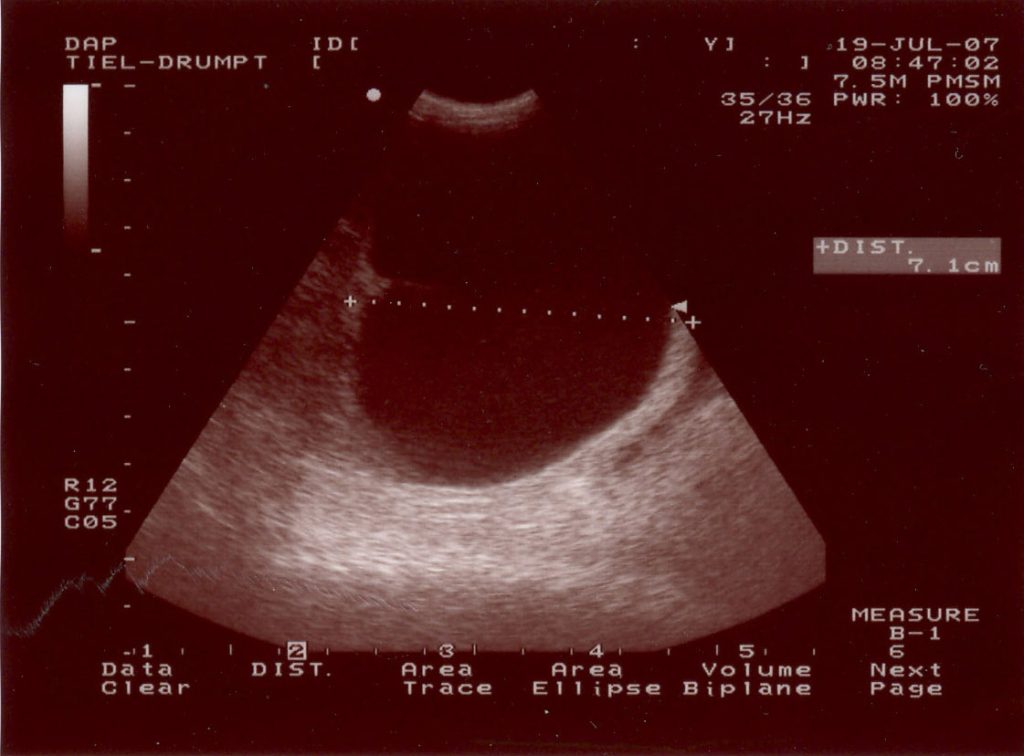

Duco is een 9 jaar oude Duitse Herder uit Tiel die sinds 1 dag toonde als een zieke hond. Hij wilde niet gaan liggen, had geen rust, was veel aan het hijgen. Bij het algemene onderzoek ontdekte de dierenarts een forse dikte in de buik. Om meer informatie over de aard van de dikte te krijgen, hebben we een echo gemaakt. We keken naar de structuur en keken of er meer loos was in de buik dan alleen deze ene bult (bijvoorbeeld uitzaaiingen van een tumor).

Aangezien Duco maar 1 testikel in zijn scrotum had (en de andere testikel dan in bijna alle gevallen in de lies of in de buikholte is ‘blijven steken’, een zogenoemde binnenbal ofwel een cryptorche testikel), was er de verdenking van een tumoreuze verandering van de testikel in de buik. (wanneer testikels in de buik of in de lies zitten zullen ze sneller tumoreus ontaarden door de hogere omgevingstemperatuur).

Hieronder ziet u een aantal foto’s van de operatie: